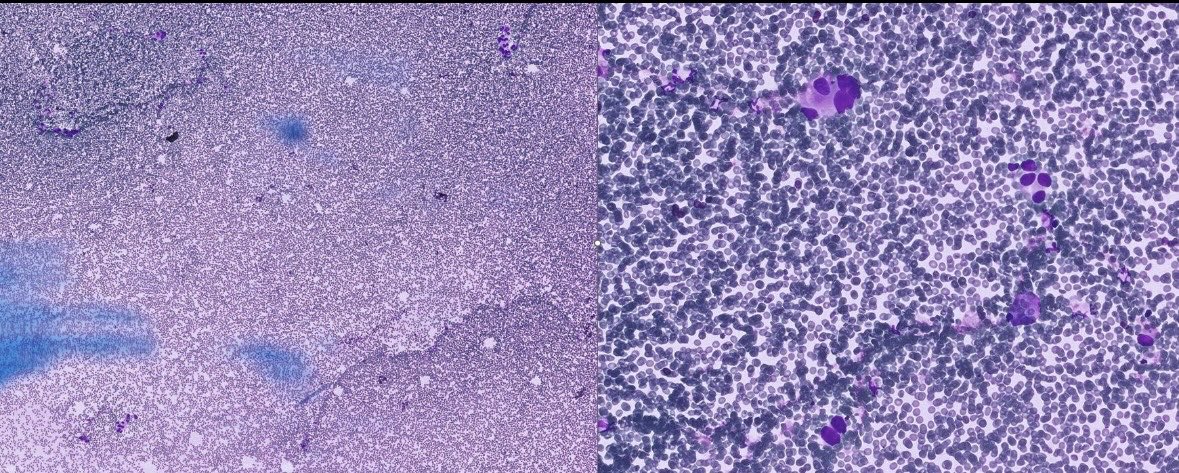

What is this? Glioma in a CSF! This can be challenging to recognize, as they look nothing like their appearance in surgical specimens! #cytology #cytopath #cytopathology #neuropath #neuropathology #pathx #pathtwitter

0

2

8